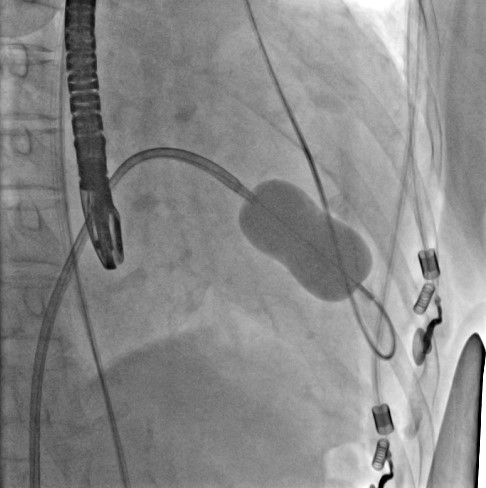

患者华法林抗凝治疗3年,INR达标情况下左房血栓仍存在,就诊于多家医院均无有效治疗手段,遂就诊于中山医院。我院食道心超提示重度二尖瓣狭窄、左房内附壁血栓形成、中度肺高压(图1)

图1. 术前食道心超